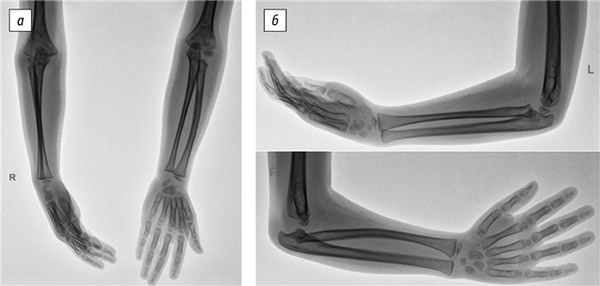

3. Рис. 3. Рентгенография локтевых суставов с захватом костей предплечья в возрасте 7 лет. Задний подвывих костей предплечья в положении сгибания: а — прямая проекция; б — боковая проекция